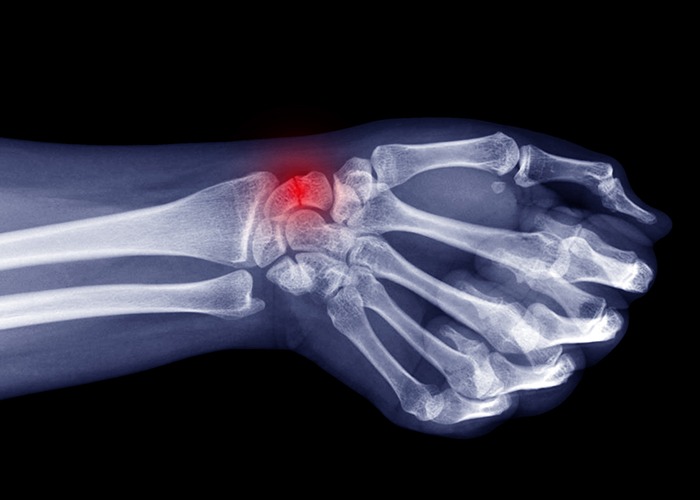

A scaphoid fracture is a common injury that occurs in the wrist, specifically in the scaphoid bone. This small bone is situated at the base of the thumb and is crucial for proper hand function. A scaphoid fracture often happens due to falls or impacts, causing immense pain and swelling in the wrist. If left untreated, this injury can lead to non-union, which means that the bone does not heal properly. Non-union occurs when the bone fails to reunite, and the lack of blood supply to the fractured area hinders the natural healing process.

To repair a scaphoid non-union, medical intervention is necessary. A surgical procedure called a bone graft may be performed, where bone tissue is taken from another area of the body or a donor and placed over the fracture site to stimulate new bone growth. In some cases, metal screws or pins may be used to stabilize the bone during the healing process. With prompt treatment and appropriate medical care, scaphoid fractures and non-unions can be effectively repaired, allowing individuals to regain their hand function and resume their daily activities.